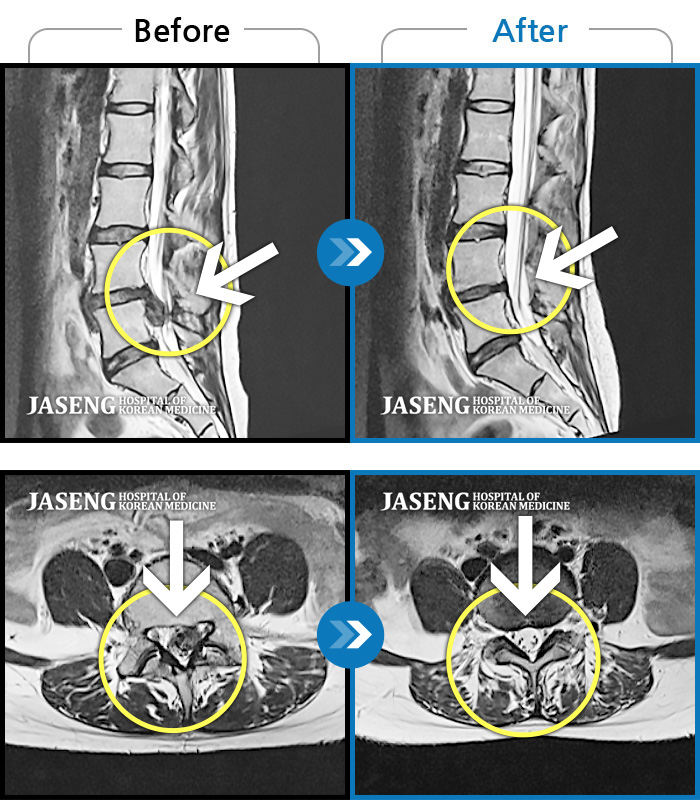

Before

After

환자에게 사전 동의를 받아 동일 조건에서 촬영되었습니다.

개인에 따라 치료 후 부작용이 발생할 수 있으니 의료진과 상담 후 치료를 진행하시기 바랍니다.

허리통증 및 하지 방사통

좌측 허리 골반 및 하지 방사통, 야간통